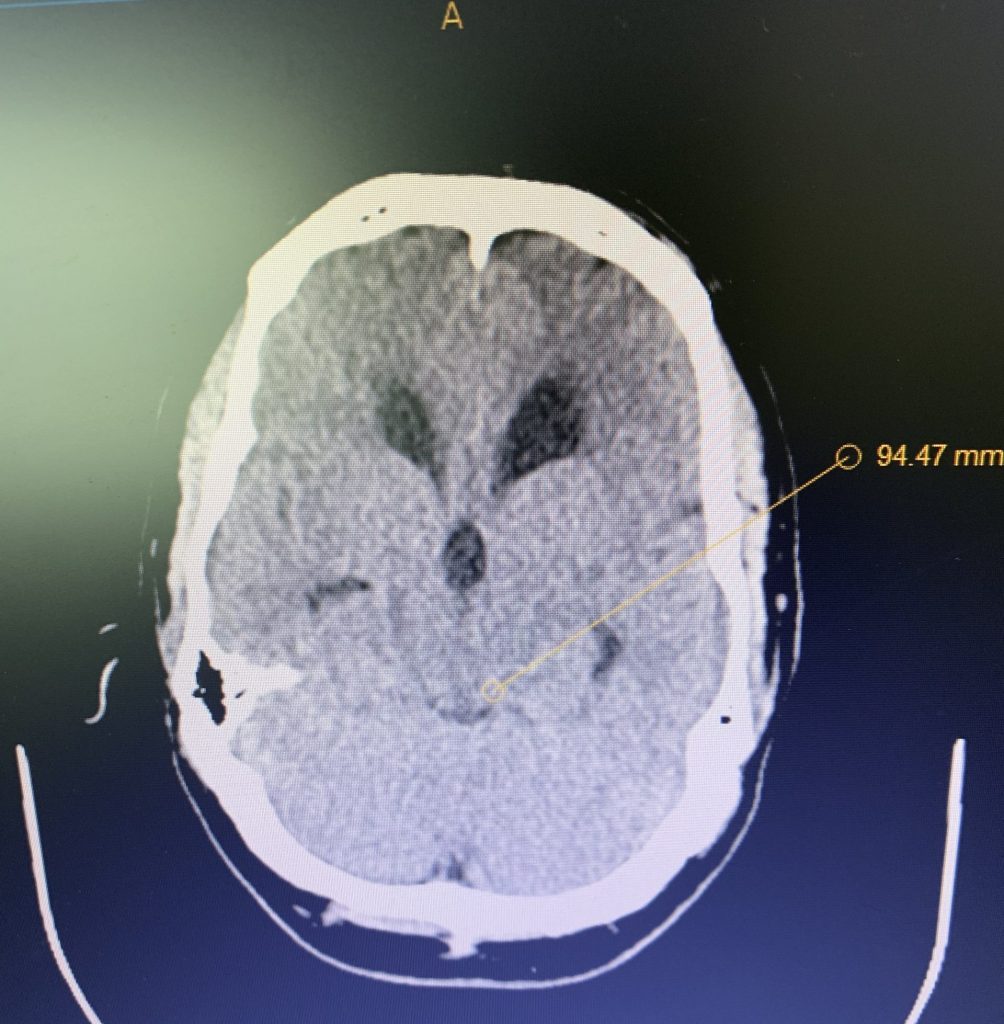

Endovascular:

Hydrocephalus and Brainstem Tumor

Author: Jonathan L. Brisman M.D., F.A.C.S., Read More!